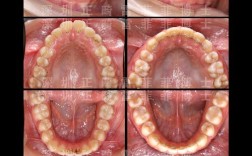

固定矫正是咬合调整的经典方式,通过托槽、弓丝及辅助装置实现精细控制,托槽的精准定位是基础:医生需依据咬合模型,将托槽粘贴于牙齿临床冠中心,确保牙齿移动过程中保持正确的长轴与倾斜度,避免因托槽位置偏差导致咬合干扰,对于深覆合患者,下颌前牙托槽可适当向龈方放置,引导牙齿垂直向伸长,打开咬合间隙。

弓丝的序列运用是关键,矫正初期使用镍钛圆丝,利用其超弹性排齐整平牙列;中期换用不锈钢方丝,通过弯制“匣形曲”“垂直曲”等,调整牙齿的转矩与轴倾度,如通过后牙“匣形曲”压低伸长的上颌磨牙,改善深覆盖;后期进行颌间牵引,通过橡皮筋连接上下颌牙弓,调整颌骨关系与牙齿位置,II类牵引(上颌牙弓牵引至下颌牙弓)可纠正下颌后缩,III类牵引则用于改善反颌,微种植体支抗的应用增强了咬合调整的精确性,通过在颌骨内植入微型钛钉,为后牙压低、前牙内收等提供稳定支抗,避免支抗丧失导致的咬合紊乱。

隐形矫正凭借可摘戴、美观的优势,成为咬合调整的重要选择,其核心在于3D打印的个性化矫正序列,每副牙套均预设牙齿移动路径,针对咬合问题,医生可在方案设计中进行针对性调整:深覆合患者可在牙套上附加“颌垫”,引导下前牙垂直向移动;反颌患者通过“过矫正”设计,在上颌前牙舌侧、下颌前牙唇侧附加附件,增强牙套对牙齿的扭转控制,逐步建立正常咬合接触。